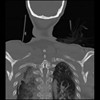

23 ANGIO,CE,Cor-MIP,5.000,ANGIO,Cor-MIP,